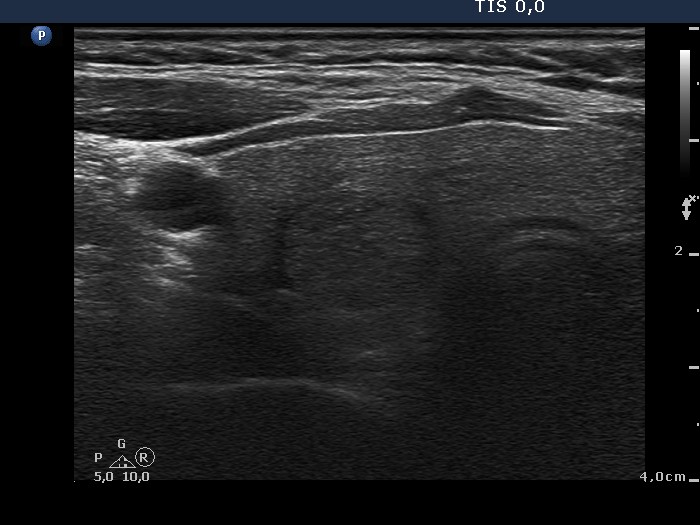

Ultrasound. The thyroid was echonormal. There were two lesions in the right lobe, the upper one was minimally hypoechogenic and had blurred borders while the nodule in the middle part of the lobe was inhomogeneous and displayed halo. Both nodules presented perinodular blood flow. The upper lesion was not noticed in the previous examination 4 years ago.

Aspiration cytology was performed from the nodule in the upper part of the right lobe. Our cytological report was suspicion of papillary carcinoma with around 10% risk of malignancy.

The lesion in question was not present four years earlier and had blurred borders. Both of these circumstances increased the likelihood of malignancy.